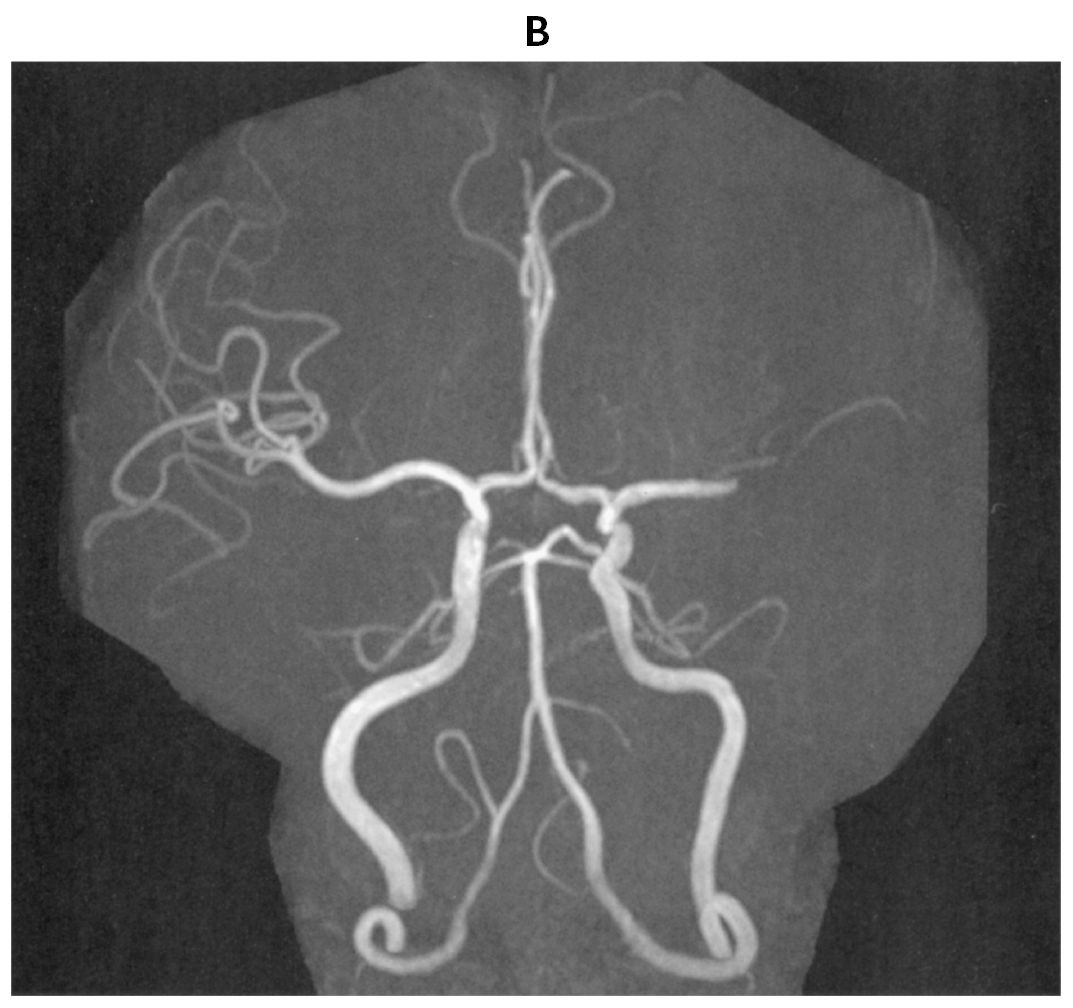

70歳の男性。65歳時に発作性心房細動を指摘されていた。農作業中に吐血し,胃潰瘍穿孔のため,入院した。開腹手術を受け,経過良好のため,退院を予定していた。手術から5日後の午後1時に突然,言葉がしゃべれなくなった。その後,右半身の脱力が出現したため,午後1時25分に病棟看護師から研修医へ連絡があった。意識レベルはJCSⅠ-2。身長171cm,体重65kg。体温36.2℃。脈拍76/分,不整。血圧170/102mmHg。左共同偏視,運動失語,右片麻痺を認めている。NIHSS〈NIH stroke scale〉は16/42点であった。血液所見:赤血球368万,Hb 9.2g/dL,Ht 35%,白血球11,600,血小板16万。12誘導心電図で心房細動を認める。午後2時の頭部単純MRIの拡散強調像(A)と頭部MRA(B)とを下に示す。